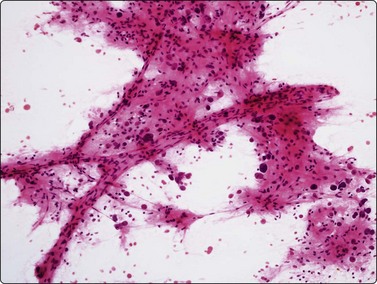

Metastatic malignancy (Figs 10.31 and 10.32)

The liver is a common site of metastatic disease because it acts as a filter. Differentiation between primary and secondary tumors on imaging can be problematic. The differential diagnosis between primary hepatocellular carcinoma and metastatic malignancy and the use of immunostaining to discriminate between them has been previously discussed in the section on HCC. Metastatic tumors may be single, multiple or diffusely infiltrating. The metastatic deposit usually shows the morphological characteristics of the primary tumor. Clinical history is very important in making the diagnosis. Review of any previous histology or cytology is recommended.

image

Fig. 10.32 Liver metastasis of colorectal carcinoma

Columnar cells arranged in glandular formation on a background of granular debris (Pap, HP).

The clinician needs to know whether liver involvement is present, either from a primary tumor which has already manifested or one which is still occult. The result of FNA will often dictate management such as chemotherapy.211 Cell typing is thus desirable in most instances. We regard it as particularly important to identify accurately those metastases which are potentially chemosensitive or hormonally manipulable. It is useful to run through a mental checklist to ensure that one is not missing germ cell tumors, neuroendocrine tumors (including small cell undifferentiated carcinomas) or carcinomas of breast, prostatic, endometrium, thyroid or even nasopharyngeal origin.

The macroscopic appearance of the aspirate is usually quite different from that of normal liver tissue. There is frequently less admixture with blood and often a high cell content. The aspirate is easily smeared into a grayish film. Necrosis may be pre-eminent, sometimes to the extent that preserved, diagnostic cancer cells are hard to find. A necrotizing metastatic tumor deposit may present as a cyst.87 If hepatocytes are found amongst the neoplastic cells, they provide a useful baseline for the evaluation of cell and nuclear size.

The cytologic patterns of metastatic carcinomas and clues to the identification of the primary site of origin are described in Chapter 5 and will not be repeated at length here. Adequate sampling is the key. Colonic adenocarcinoma is probably the most common source of liver metastases. The cytological pattern is characteristic, showing malignant columnar epithelial cells in palisaded rows or microglandular groups with a background of necrotic debris (Fig. 10.32), often with evidence of mucin secretion.35 Small cell undifferentiated carcinoma of pulmonary or colonic derivation often involves the liver diffusely. Hepatocytes may be numerous and evenly dispersed between tumor cell groups in smears. Hepatic FNA in these cases has staging value in anticipation of chemotherapy.212 Carcinoid tumors of bronchogenic, pancreatic or colonic origin are distinguishable from metastatic adenocarcinoma by their endocrine appearance. The nuclei have a rounded shape with ‘speckled’ granular, hyperchromatic chromatin. Red (MGG) cytoplasmic granularity may be visible. The diagnosis can be confirmed by immunoperoxidase staining for neuroendocrine markers.213